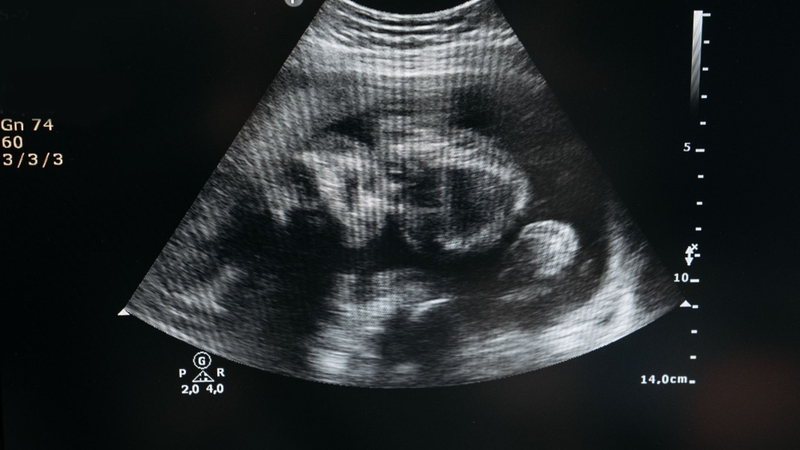

Dù nguyên nhân không rõ ràng, việc phát hiện sớm tình trạng dây rốn bám mép qua siêu âm là rất quan trọng. Mẹ bầu sẽ được theo dõi chặt chẽ với siêu âm Doppler mạch máu, để bác sĩ có thể nắm rõ tình trạng của thai nhi và lên kế hoạch sinh đẻ phù hợp.

Dây rốn bám mép là một tình trạng bất thường có thể gây ảnh hưởng lớn đến sự phát triển của thai nhi. Việc phát hiện sớm qua siêu âm định kỳ là vô cùng quan trọng để mẹ bầu có thể theo dõi và thực hiện các biện pháp chăm sóc phù hợp. Mẹ bầu cần chú ý đến việc thăm khám và siêu âm để phát hiện các vấn đề bất thường về dây rốn, từ đó đảm bảo sức khỏe cho cả mẹ và bé trong suốt thai kỳ.